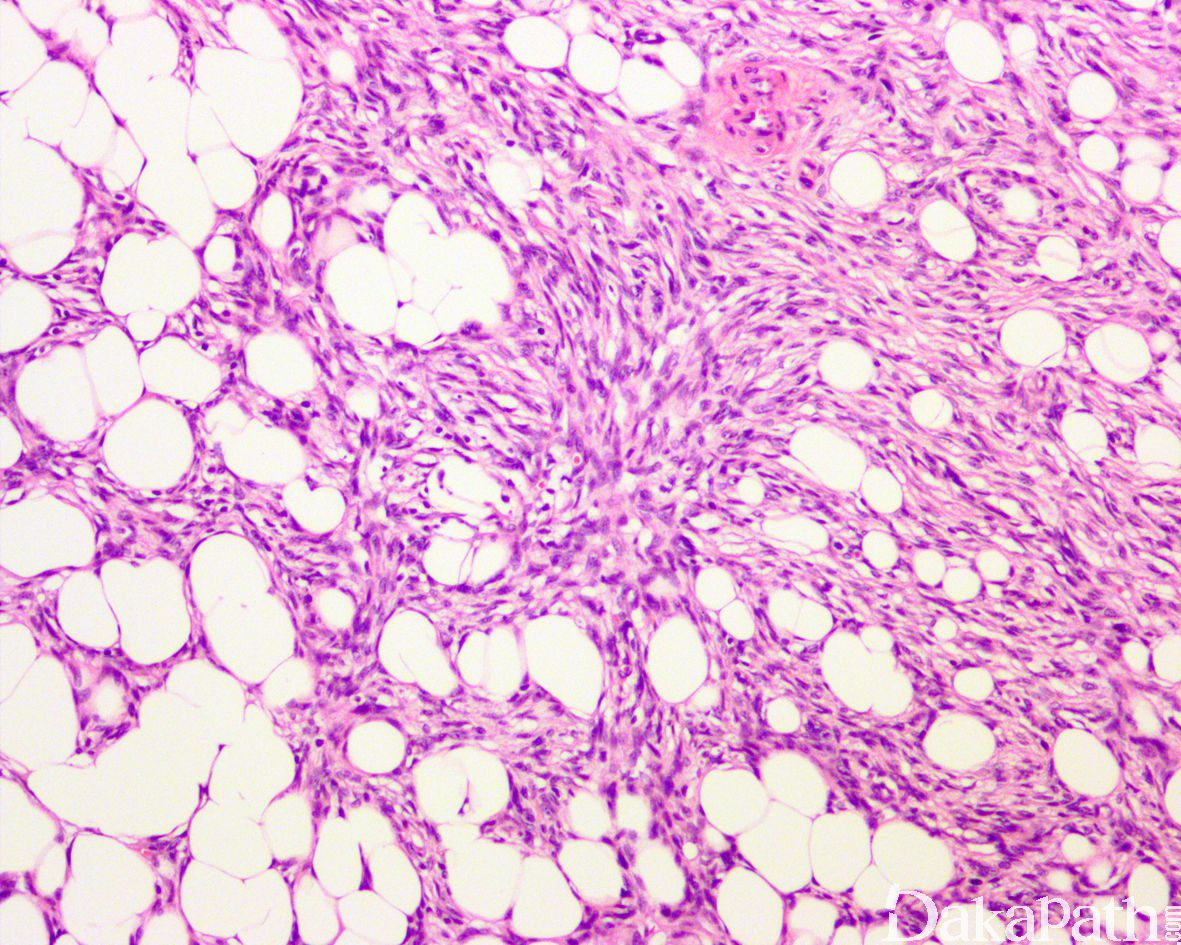

肿瘤主要位于真皮层,弥漫浸润性生长,浸润脂肪组织形成特征性的蜂窝状或蕾丝样 (或称花边样)浸润图像;

瘤细胞均匀较一致,呈两端细长的纤维母细胞样,呈一致的致密的席纹状排列,少数病例内可见局灶的血管外皮瘤样排列;

瘤细胞常紧密围绕残留的汗管等皮肤附件组织;